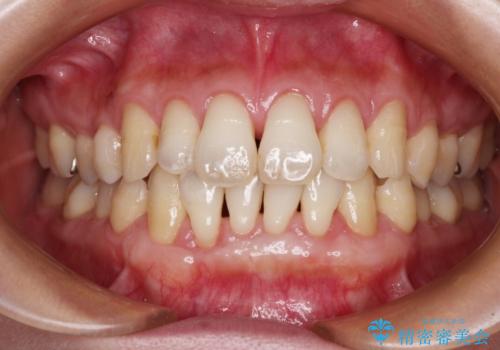

上顎両側から歯肉を採取したたため、術後は痛みや出血で辛い思いをされましたが、1回の処置で満足のいく結果となりました。

根面被覆量も改善できましたが、歯肉の厚みが十分なものとなったことで、今後の歯肉退縮に歯止めをかけることができました。